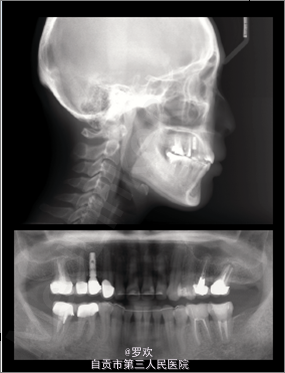

治疗后露龈笑明显改善,患者对面型满意,上下前牙舌侧丝固定保持。 种植钉的出现为很多疑难病例提供了简单的处理方法,为正畸医生提供了另一片天地,可以多尝试种植钉的使用